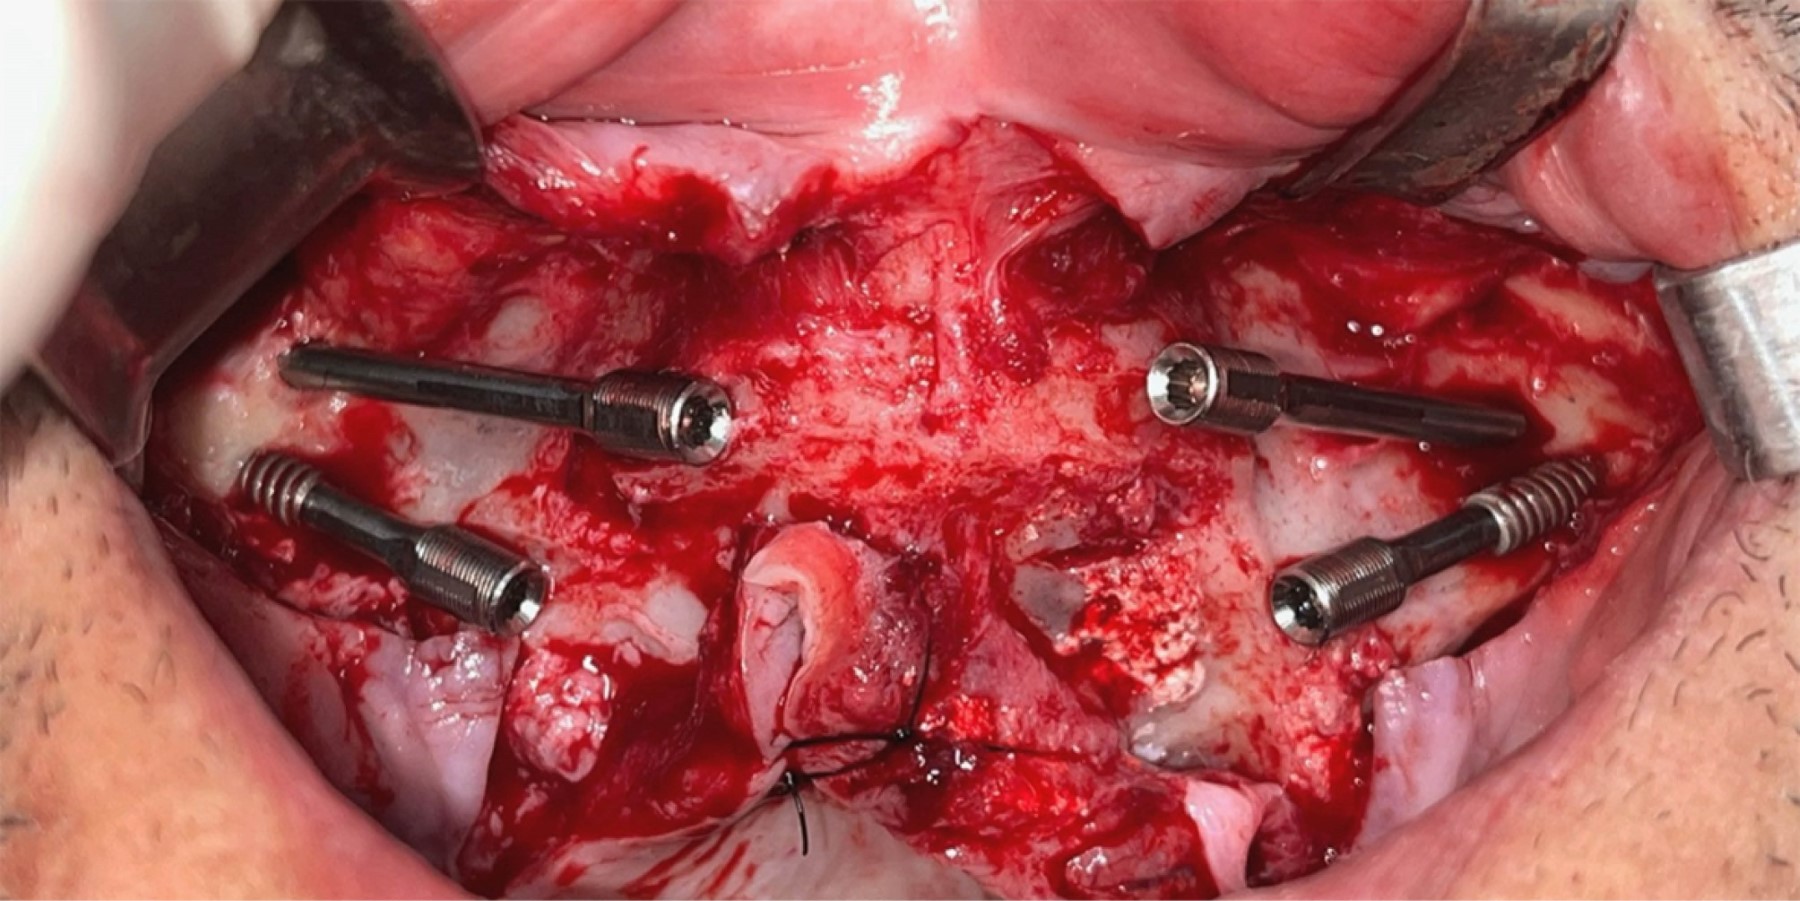

El caso que se ilustra presenta la necesidad de avanzar el maxilar para compensar la discrepancia sagital y, además, dificultad para colocar implantes cigomáticos por tener poco espacio y anatomía desfavorable del hueso malar, muy delgado y de gran concavidad respecto a la delgada cresta residual. Se realizaron guías de perforación, osteotomía y fresado. Los implantes yuxtaóseos se diseñaron de manera tal que combinan osteosíntesis del avance maxilar y portadores de los pilares protésicos para la reconstrucción dentomaxilar.

Se decidió un abordaje combinado con osteotomía tipo Le Fort I, con avance maxilar de 10 mm, y colocación de implantes yuxtaóseos personalizados, planificados digitalmente con base en la anatomía remanente. Esta decisión quirúrgica se justificó por la precariedad volumétrica de los huesos malares, que impedía el anclaje bicortical cigomático, sumado a la contraindicación por patología sinusal crónica (Figuras 4, 5, 6 y 7). El procedimiento fue realizado bajo anestesia general, sin complicaciones, utilizando guías quirúrgicas. La cirugía concluyó con procedimiento complementario de ritidectomía (Figura 8).